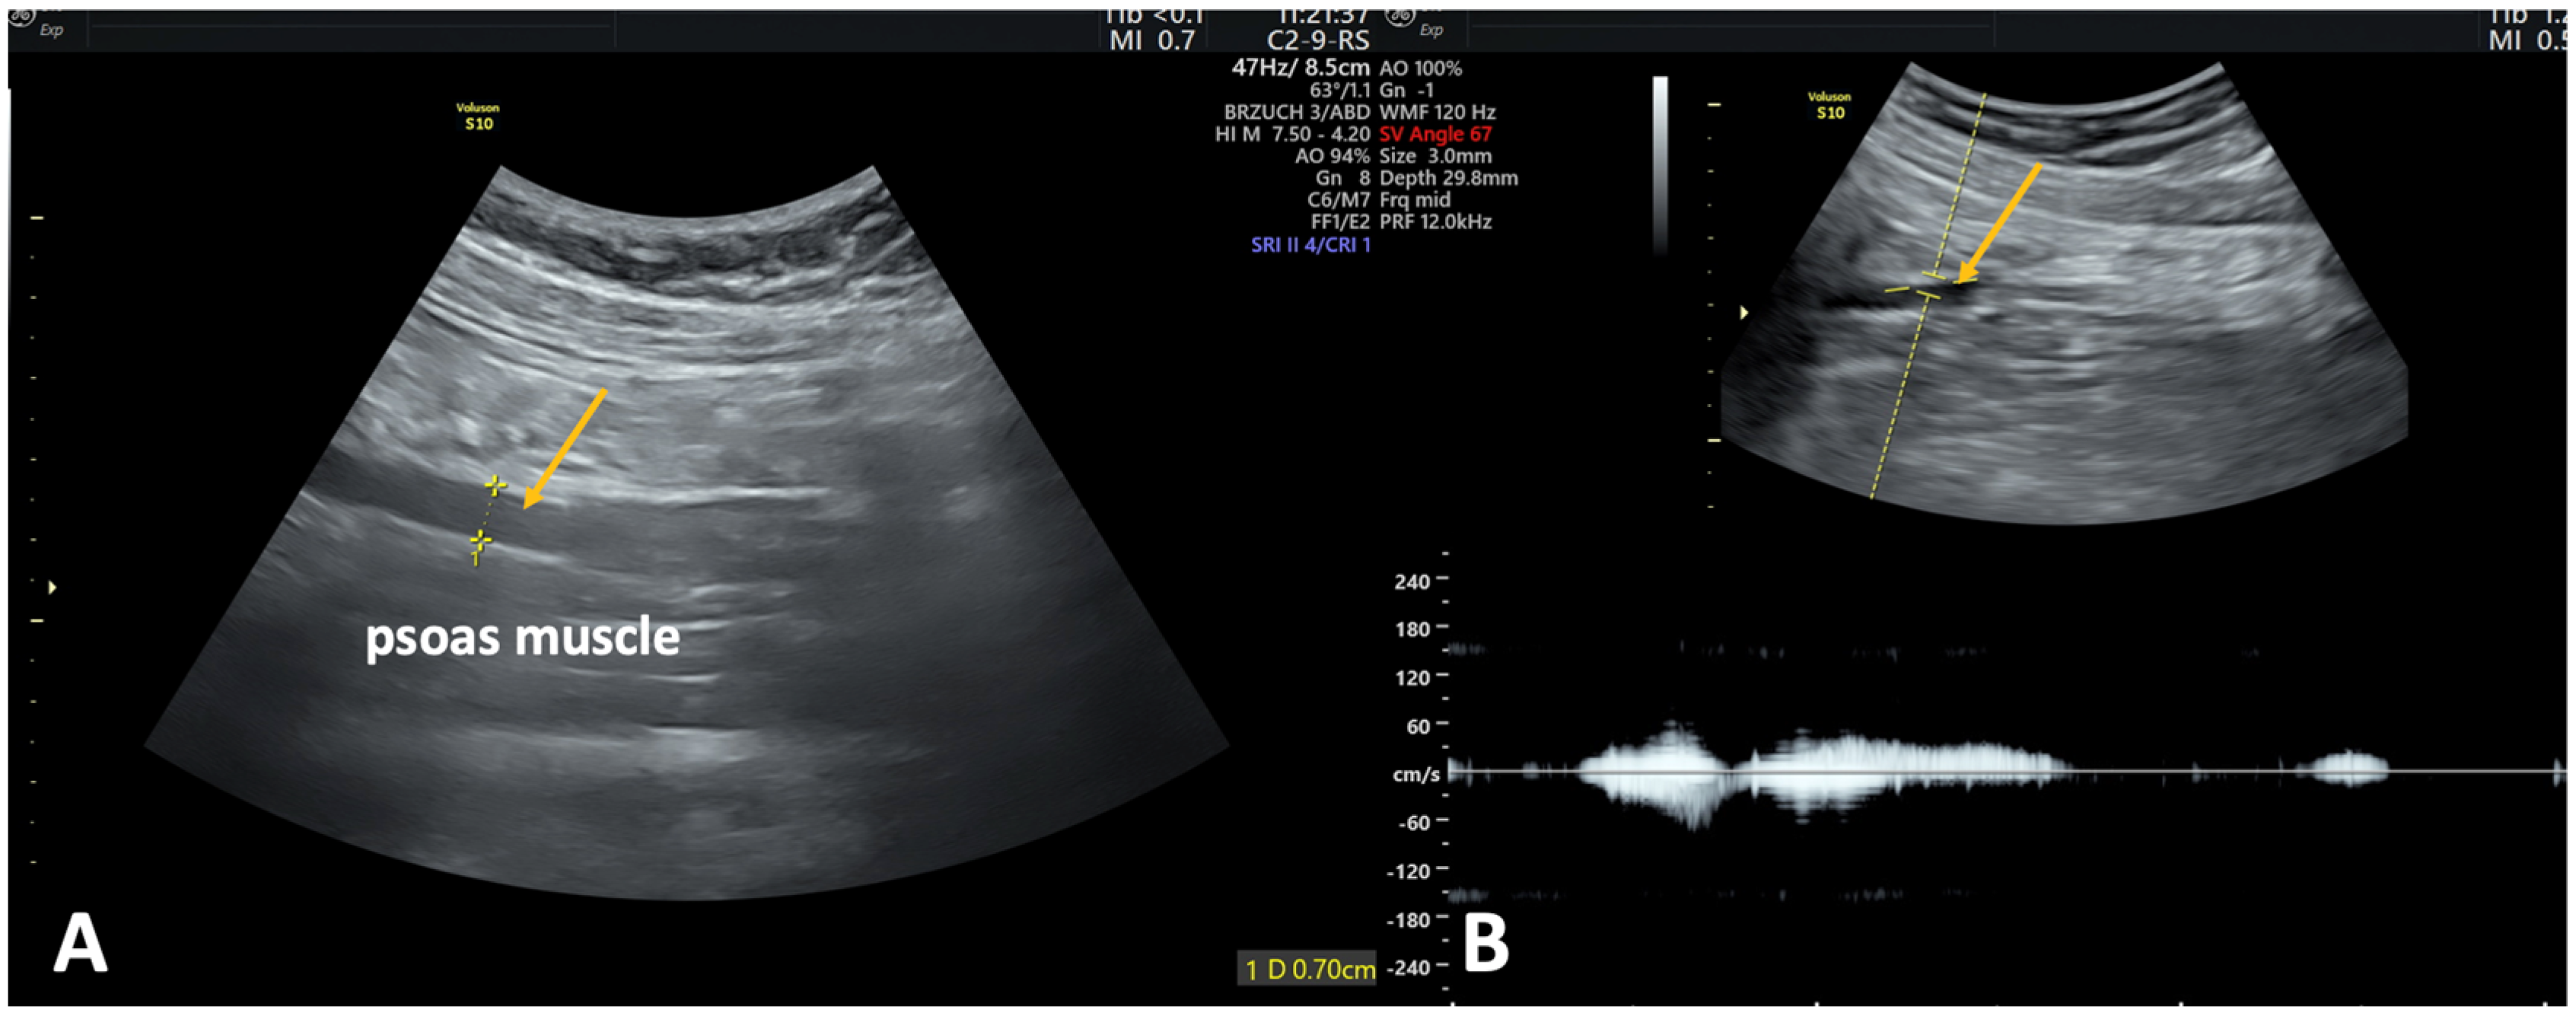

2.2.2. Transabdominal Ultrasonography